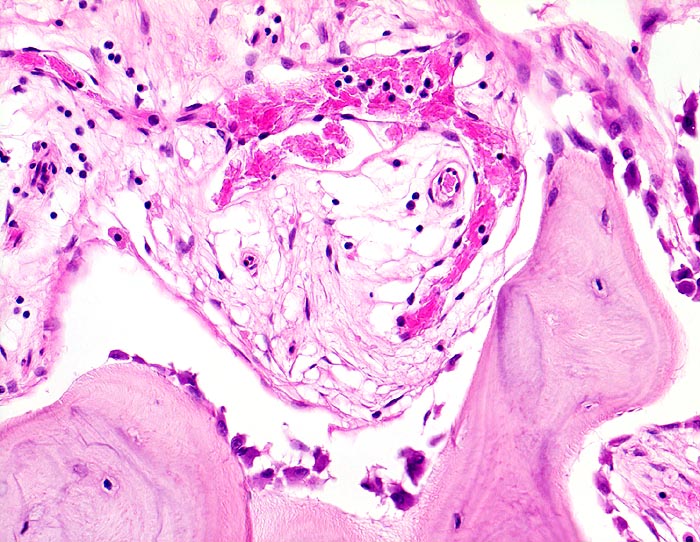

PathoPic – image database / PathoPic ID 4505 - Morbus Paget des Knochens

Morbus Paget des Knochens

Knochen, Tibia

Zone mit gesteigertem Knochenanbau. Das Spongiosabälkchen ist von einer Osteoblastentapete bedeckt, welche neuen Knochen anbauen. Das Mark zeigt eine lockere Fibrose mit vermehrten kapillären Gefässen.

Die Patientin hatte wiederholt über Knieschmerzen geklagt. Autoptisch zeigte das Kniegelenk eine leichte Arthrose. Aus der auffallend verdickten Tibia wurde eine Gewebsprobe zur Untersuchung entnommen.

Histologie

200